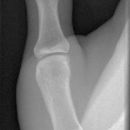

Bennett Fraktur

Es wurden keine Bilder gefunden.